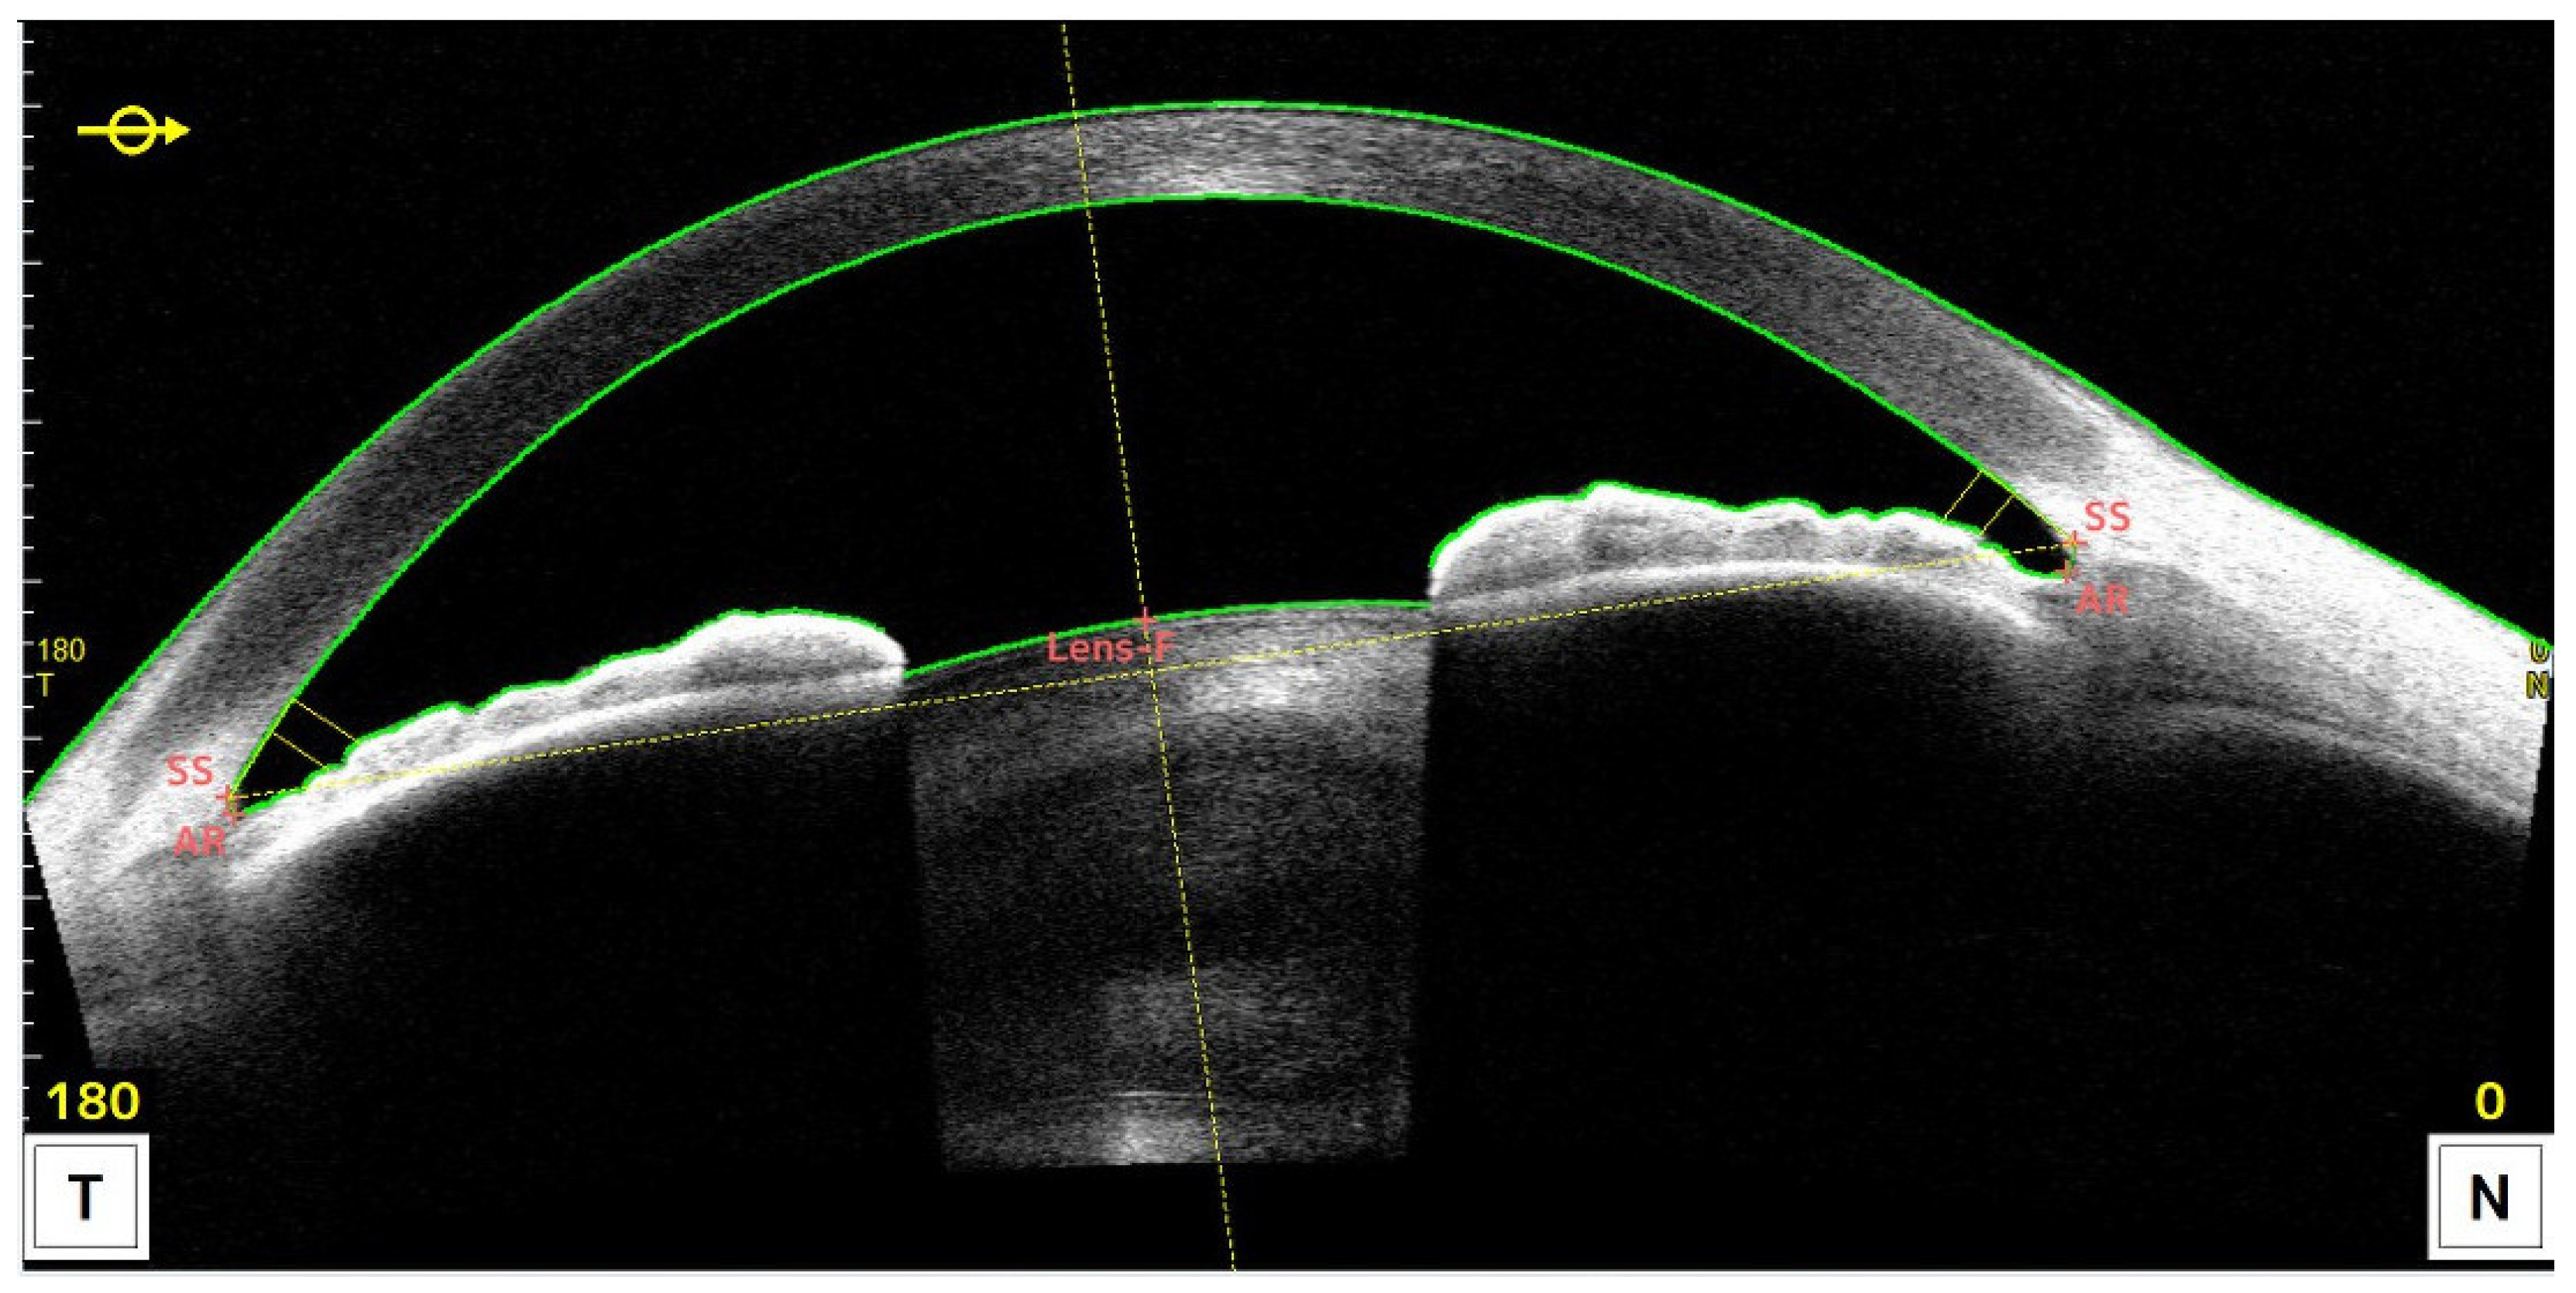

2.2. Measurement Method